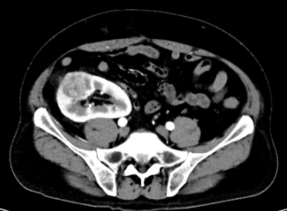

image.png CT检查提示右侧移植肾肿瘤

来自河南的56岁李先生五年前因肾衰竭接受了肾移植手术。术后,李先生的移植肾功能稳定。然而,近期的体检结果却令他如坠冰窟:移植肾内有一个肿瘤。针对这种情况,业内多推荐行传统的肾脏根治性切除术。但如果切除移植肾,患者将不得不再次依赖透析生存。带着最后的希望,李先生慕名来到上海仁济医院泌尿科就诊,希望能保住这个珍贵的肾脏。